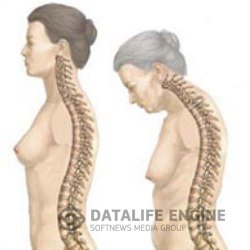

Болезнь БехтереваЭтот недуг считают неизлечимым. Его вызывают дисфункция почек, неполадки в желчном пузыре и печени, протоки... Болезнь БехтереваЭтот недуг считают неизлечимым. Его вызывают дисфункция почек, неполадки в желчном пузыре и печени, протоки...